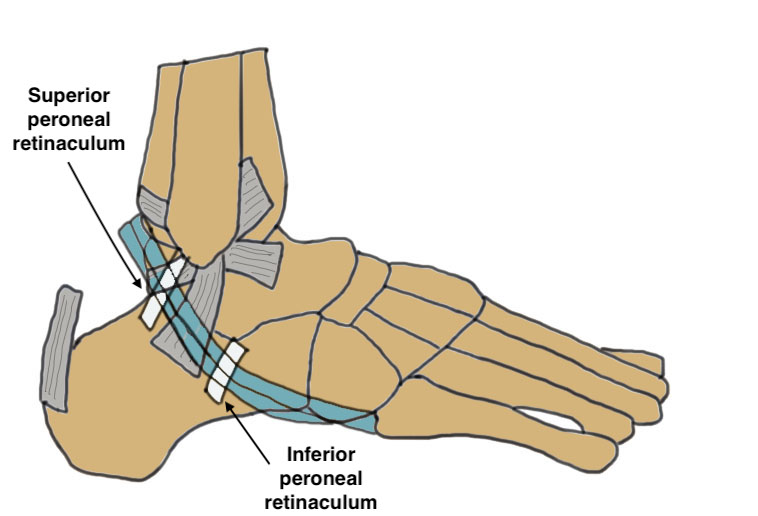

Anatomy

The ankle is a uniaxial joint that resembles a mortise and tenon

- very stable when loaded in the neutral position

- bony contact and stability decrease with plantar flexion